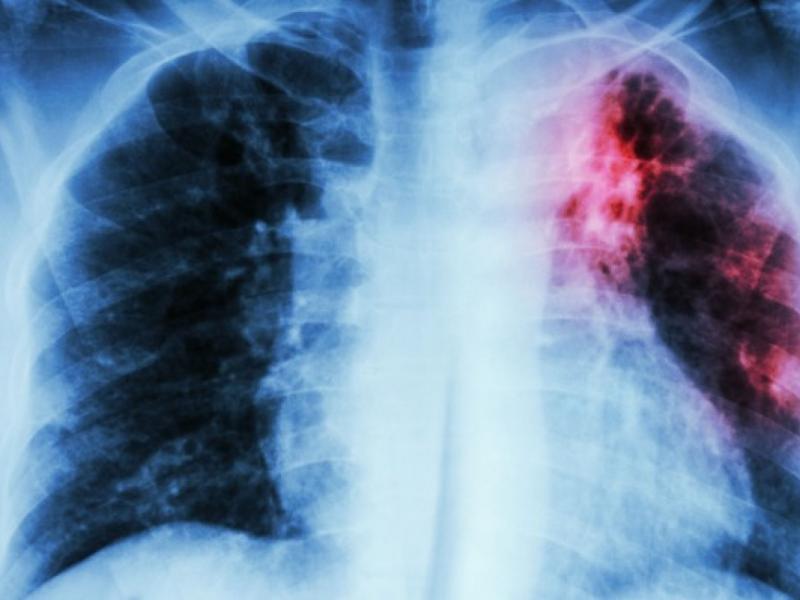

Το Google Health ερμηνεύει τις ακτινογραφίες των πνευμόνων εξίσου καλά με έμπειρους ακτινολόγους

Ένα νέο σύστημα τεχνητής νοημοσύνης της Google ερμηνεύει τις ακτινογραφίες των πνευμόνων εξίσου καλά με έμπειρους ακτινολόγους